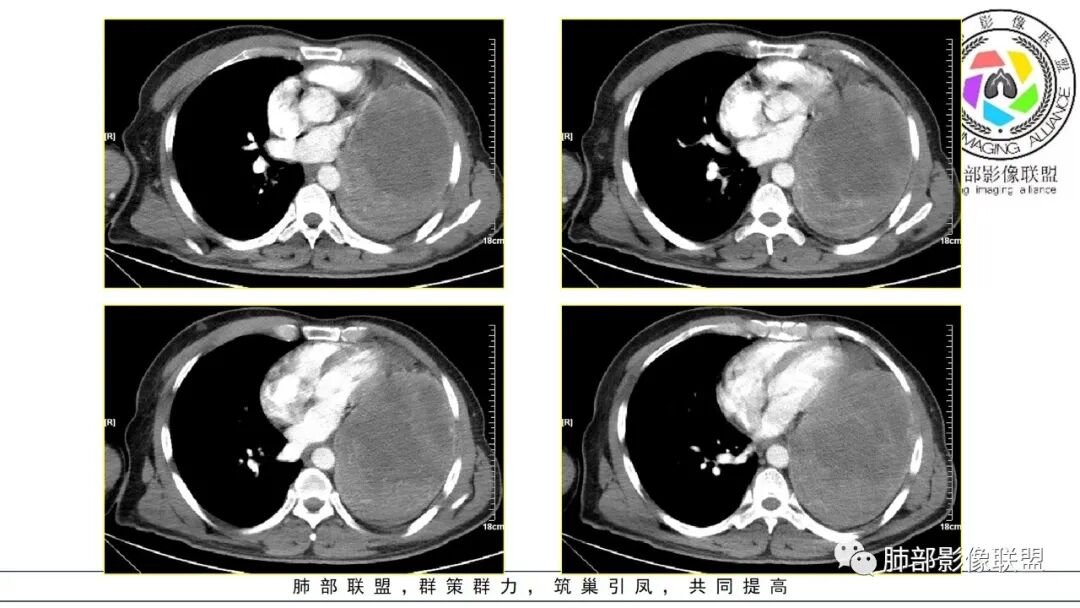

左肺巨大肿块,边缘光滑,密度不均,内可见多发低密度坏死,坏死边缘清晰,左肺支气管受压变窄闭塞,考虑左肺肉瘤样癌?鉴别滑膜肉瘤?

左肺巨大肿块,气管受压闭塞并受侵犯,有坏死和粗大钙化,考虑恶性,肉瘤样癌,待排滑膜肉瘤,平滑肌肉瘤等

定位肺内,左下肺巨大肿块,边缘光整,密度不均,边缘少许钙化,中心坏死,外周强化,左肺支气管及心脏受压,考虑肉瘤样癌,鉴别滑膜肉瘤,SFT

左肺巨大肿块,密度不均,边缘清晰,内有坏死和粗大钙化,不均匀强化,气管堵塞,考虑恶性,肉瘤样癌,鳞癌。

左肺巨大肿块,边缘光滑清晰,内见多发低密度影,边界也比较清楚,左肺支气管受压变窄闭塞,恶性。

左侧胸腔巨大软组织肿块,边缘膨隆、清晰,临近血管及气管受压推移,肿块内密度不均匀,见大片状坏死及条形钙化,增强后不均匀强化,考虑恶性,定位肺内,肉瘤样癌可能大,定位肺外,纵隔来源恶性鞘瘤,胸膜来源sft

成年人,左肺巨大肿块,气管,支气管受压闭塞及被推挤,病灶内有坏死和钙化,增强病灶明显不均匀强化,考虑外向内生长的恶性病变,肉瘤样癌,癌肉瘤,滑膜肉瘤,平滑肌肉瘤等

男,50岁,双下肢水肿10余天,发热3天。NSE、细胞角蛋白19片段增高。胸部CT:肺气肿背景,左下叶巨大肿块,边缘膨隆明显,与周围界限清楚,累及左肺门、左上叶,上叶支气管受压狭窄,下叶支气管截断,不均匀强化,湖泊样坏死,肿块边缘粗大点状钙化,肿块内血管影迂曲、模糊,蛇纹?考虑恶性,鳞癌?肉瘤样Ca?鉴别SFT。